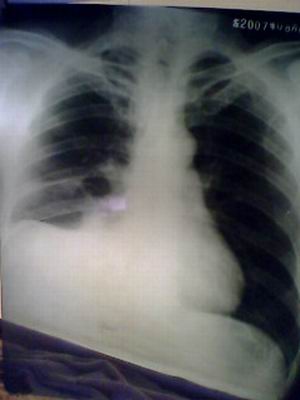

标题: X2591:典型肺底积液 [打印本页]

标题: X2591:典型肺底积液

支持右侧肺底积液,性质待查,建议进一步检查,请注意结合临床。

右肺底积液。

右侧心隔角区模糊不清,右叶间胸膜增厚,右隔顶外移。支持肺底积液,右肺中叶炎变?

应该是,最高点在外三分之一.

肺底积液:积液位于肺底与膈之间的胸膜腔,右侧较多见.被肺底积液向上推挤的肺下缘呈圆顶形状,圆顶最高点位于偏外1/3且肋膈角深而锐利.